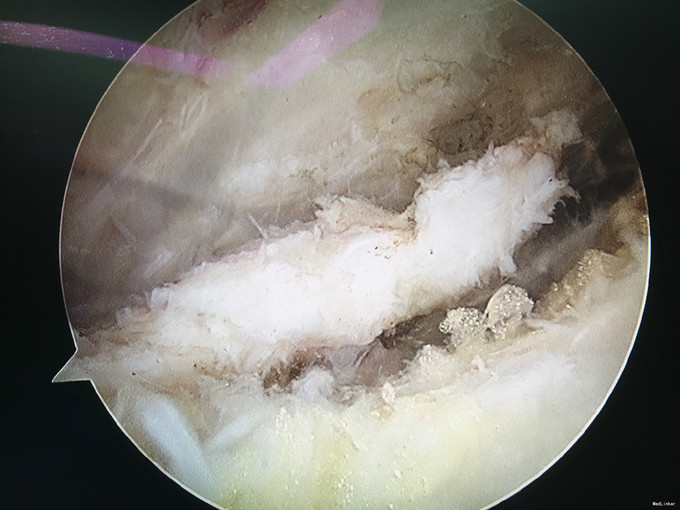

诊断:类风湿性关节炎 治疗:右膝关节镜下清理

随访:患者术后早期术膝肿胀消除明显,活动度较术前明显改善。患者继续至风湿免疫科行内科治疗。 讨论:对风湿性疾病的局部症状治疗,关节镜手术治疗不失为一实用而又有效的治疗方法。